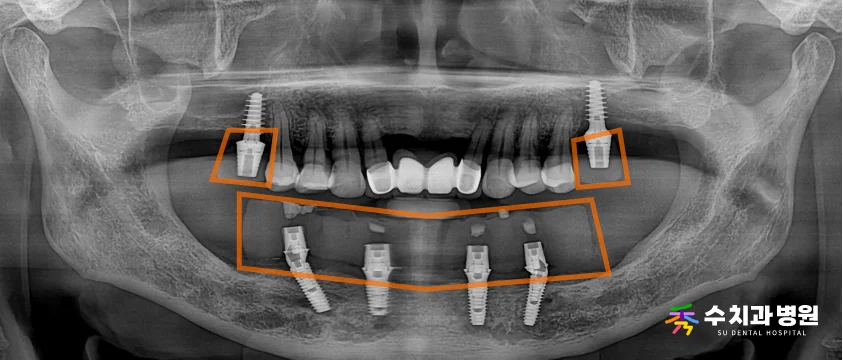

방사선 및 3D CT 검사를 통해 꼼꼼히 확인해 본 결과,

아래턱은 잇몸뼈 흡수가 심하고 신경선이 가깝게 지나가,

어금니 쪽에 임플란트를 심기 위한 뼈가

절대적으로 부족한 상태였습니다.

또한 위턱 양쪽 어금니도 모두 상실된 상태여서,

전반적인 구강 기능의 회복이 시급한 상황이었습니다.

위턱 양쪽 어금니 부위에는 각각 임플란트를 식립하고,

뼈가 부족한 아래턱은 신경관을 피해 앞쪽에만

4개의 임플란트를 심는

전체 임플란트(All-on-4)를 계획했습니다.

특히 아래턱의 가장 뒤쪽 임플란트는 사선으로 기울여 심어,

어금니가 받는 씹는 힘을 튼튼하게 지지하도록 설계했습니다.

좁은 잇몸뼈와 신경관의 위치를 안전하게 피하기 위해,

3D CT 분석을 바탕으로 네비게이션 가이드를 사전 제작하여

정밀한 수술을 진행하기로 환자분과 상의했습니다.